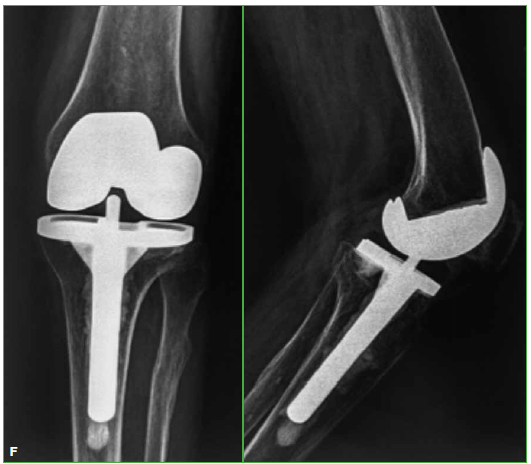

Figura. F.

Evolucion a los 7 años, sin signos de aflojamiento.